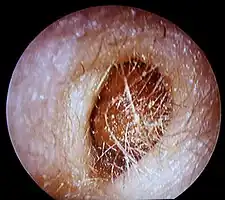

Bouchon de cérumen complet dans le conduit auditif

- Corps étrangers (morceau de coton, insecte...) et bouchon de cérumen